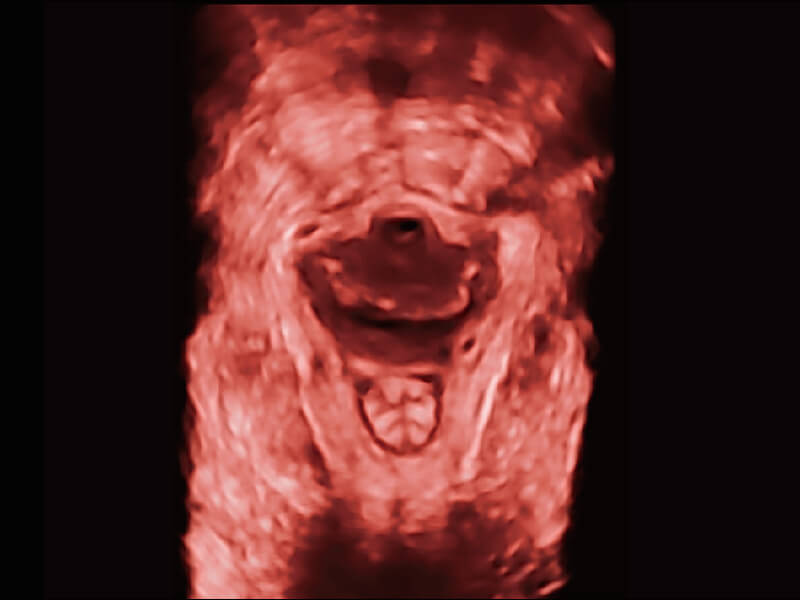

S60探头工艺,从前端信号处理每一个环节采集无损声学数据,真实还原组织原貌,再现解剖细节。

超宽频带技术,为容积成像带来优质的二维图像基础,为您呈现丰富的结构细节,栩栩如生地展示宝宝的宫内形态以及各种组织的立体结构。